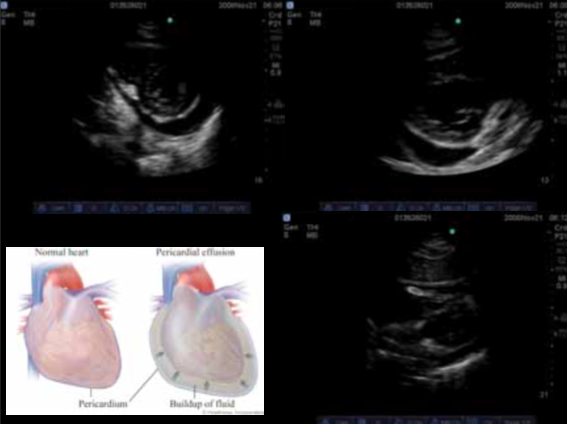

What does this patient have?

Pericardial effusion, note the fluid going around the heart

How do differentiate a pleural effusion from a pericardial effusion

Pericardial effusion has “rat tail” that goes between the heart and descending aorta. The pleural effusion goes behind the aorta.